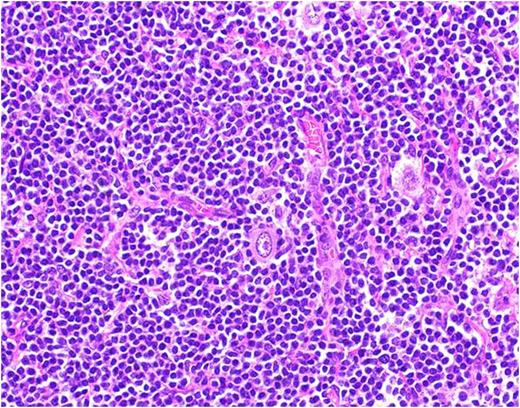

A 59 year old male with no significant medical history presented with progressive swelling and erythema of the right testis. Testicular cancer was suspected and he underwent a radical right inguinal orchiectomy. Pathology revealed a 5.7cm seminoma of the testis with lymphovascular invasion and without spermatic cord involvement (pT2) (Fig. 1). His tumor markers including AFP, LDH, and Beta-HCG were normal (S0). A CT scan of the chest, abdomen and pelvis followed by a PET/CT revealed enlarged, hypermetabolic mediastinal, hilar and periportal lymphadenopathy interpreted by the radiologist as concerning for metastatic disease. Given the atypical distribution for lymphadenopathy from testicular seminoma, an excisional biopsy of a left hilar node was performed and revealed Classical Hodgkin Lymphoma with IHC positive for CD15, CD30 and PAX-5 (Fig 2). He denied any B-symptoms and his bone marrow was uninvolved by lymphoma (stage IIIA). Adjuvant therapy for his germ cell tumor, otherwise an important consideration, was deferred and he began chemotherapy with adriamycin, bleomycin, vinblastine and dacarbazine (ABVD) for 6 cycles. Interim PET/CT after 2 cycles of ABVD showed a complete response. He has completed 6 cycles of ABVD and chose observation as opposed to single dose of adjuvant carboplatin for his seminoma and is currently under surveillance for both malignancies.

Lymph node biopsy- Classic Hodgkin's lymphoma